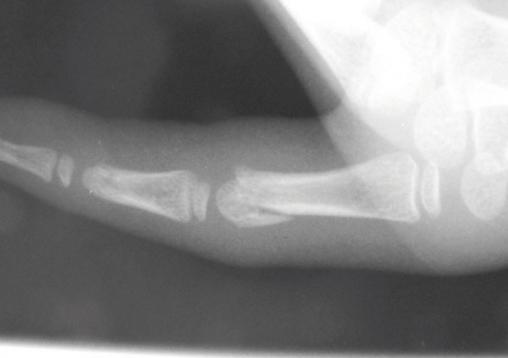

© Frank Fitoussi, La Revue du Praticien Fracture du col de la première phalange avec bascule dorsale. Voir : Fitoussi F. Particularités des traumatismes de la main de l'enfant. Rev Prat 2013;63:1253-7.